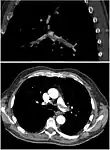

CT pulmonary angiography (CTPA) is a pulmonary angiogram obtained using computed tomography (CT) with radiocontrast rather than right heart catheterization. Its advantages are that it is accurate, it is non-invasive, it is more often available, and it may identifying other lung disorders in case there is no pulmonary embolism. The accuracy and non-invasive nature of CTPA also make it advantageous for people who are pregnant.[51]

Assessing the accuracy of CT pulmonary angiography is hindered by the rapid changes in the number of rows of detectors available in multidetector CT (MDCT) machines.[52] According to a cohort study, single-slice spiral CT may help diagnose detection among people with suspected pulmonary embolism.[53] In this study, the sensitivity was 69% and specificity was 84%. In this study which had a prevalence of detection was 32%, the positive predictive value of 67.0% and negative predictive value of 85.2%. However, this study's results may be biased due to possible incorporation bias, since the CT scan was the final diagnostic tool in people with pulmonary embolism. The authors noted that a negative single slice CT scan is insufficient to rule out pulmonary embolism on its own. A separate study with a mixture of 4 slice and 16 slice scanners reported a sensitivity of 83% and a specificity of 96%, which means that it is a good test for ruling out a pulmonary embolism if it is not seen on imaging and that it is very good at confirming a pulmonary embolism is present if it is seen. This study noted that additional testing is necessary when the clinical probability is inconsistent with the imaging results.[54] CTPA is non-inferior to VQ scanning, and identifies more emboli (without necessarily improving the outcome) compared to VQ scanning.[55]

CT pulmonary angiography showing a "saddle embolus" at the bifurcation of the main pulmonary artery and thrombus burden in the lobar arteries on both sides.